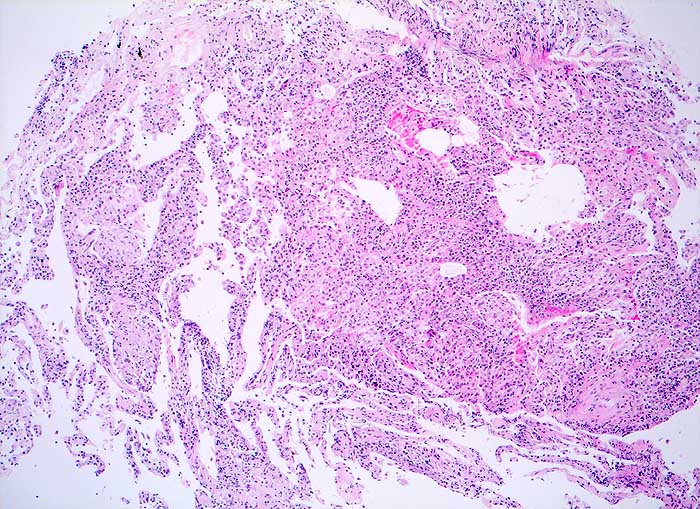

Exogen allergisch Alveolitis

Alveoläres Lungengewebe mit mässig bis deutlich ausgeprägter interstitieller Entzündung und einigen lockeren intraalveolären Granulomen. Herdförmige geringe interstitielle Fibrose. Geringe Alveolarzellretention.

Broncho-alveoläre Lavage: Massive Lymphozytose und deutliche Vermehrung der Alveolarmakrophagen mit schaumzelliger Umwandlung. Mässige Eosinophilie und deutliche Vermehrung der Mastzellen.

Die Vermehrung der Alveolarmakrophagen mit schaumzelliger Umwandlung in der BAL passt zu dem hier histologisch beobachteten Befund der Alveolarzellretention, was bei der exogen-allergischen Alveolitis häufig zu beobachten ist.